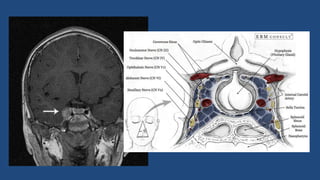

Disseminação Intracraniana

TROMBOSE DO SEIO CAVERNOSO

• O seio cavernoso é um dos seios da dura

máter que drenam o sangue venoso

cerebral

• Área onde passam estruturas anatômicas

importantes:nervos troclear, oculomotor,

oftálmico,maxilar, abducente e carótida

interna

• Infecções chegam a essa região via plexo

pterigóideo e veia oftálmica inferior

• Sinais e sintomas: oftalmoplegia, midríase

paralítica,ptose palpebral

• Alta taxa de mortalidade

• Tratamento: antibioticoterapia agressiva

Disseminação Intracraniana TROMBOSE DOSEIO CAVERNOSO • O seio cavernoso é um dos seios da dura máter que drenam o sangue venoso cerebral • Área onde passam estruturas anatômicas importantes:nervos troclear, oculomotor, oftálmico,maxilar, abducente e carótida interna • Infecções chegam a essa região via plexo pterigóideo e veia oftálmica inferior • Sinais e sintomas: oftalmoplegia, midríase paralítica,ptose palpebral • Alta taxa de mortalidade • Tratamento: antibioticoterapia agressiva